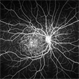

- retinal dystrophy

- Scanning laser ophthalmoscope

- 34 year old male with colour blindness and loss of visual field